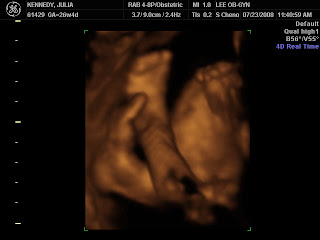

Another not clear shot of her feet crossed,

kicking back in the womb. Not really, her face is blurred behind.

Ouch...that can't be comfortable?

A little high, but she's practicing doing "SK in thought".

That is her Rockett Kick going on too, little foot in the air.